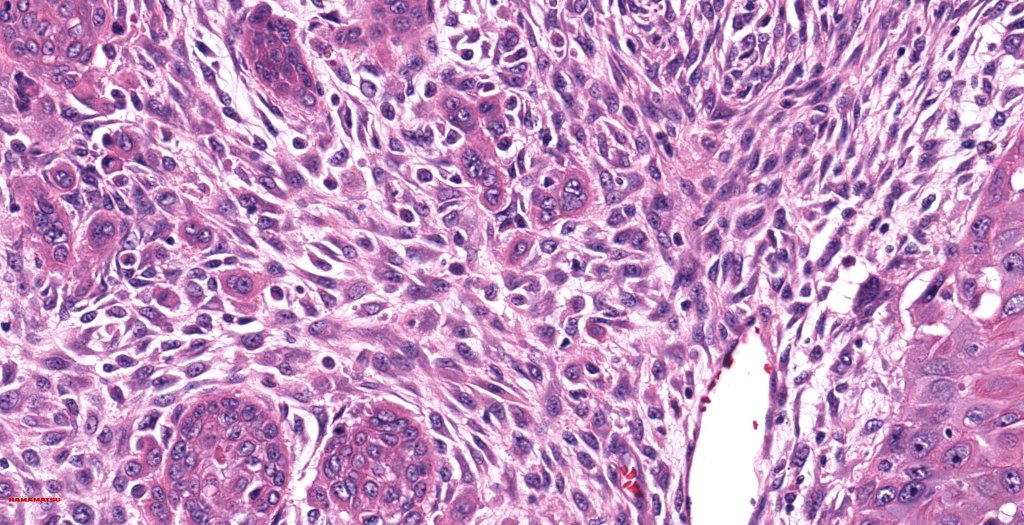

•Biphasic tumor

•Possible epithelial to mesenchymal transition

•Admixture of squamous carcinoma & pleomorphic spindled cell, osteoid, chondroid, MFH-like +/- osteoclast-like giant cells & rarely, smooth muscle, skeletal muscle, myofibroblastic or angiosarcomatous elements

•Epithelial component AE1/AE3, CK5/6 & p63 +ve;

•Mesenchymal element variable CD10, CD68, CD99 & lineage specific markers +ve; scattered cells may show weak keratin expression